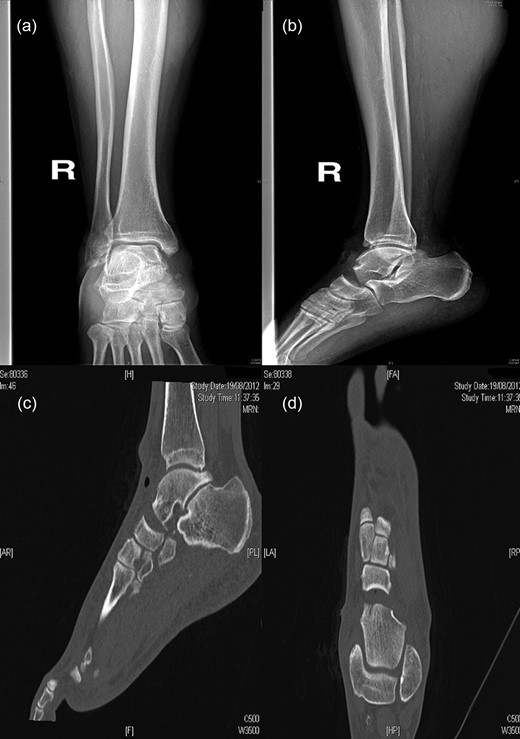

The patient underwent a first-time surgical repair. Abundant washing of the lacerated wound with saline solution and chlorhexidine was done. Injuries of dorsalis pedis artery, tibialis anterior tendon, estensor digitorum longus tendons, peroneus tertium tendon were revealed, with the loss of talus head and with a complex lesion of the talonavicular ligament. Tendinous structures damaged were surgically sutured and subsequently an antibiotic-loaded cement spacer was positioned into the bone gap to re-establish the joint congruence. The foot was put in a cast and kept non-weight bearing for 8 weeks (Fig. 2).

An image of the foot before the first-time surgical repair reveals the injuries of dorsalis pedis artery, tibialis anterior tendon, estensor digitorum longus tendons, peroneus tertium tendon, with the loss of talus head and with a complex lesion of the talonavicular ligament. (a) Tendinous structures damaged were surgically sutured and subsequently an antibiotic-loaded cement spacer was positioned into the bone gap to reestablish the joint congruence (b). AP (c) and lateral (d) radiographs of the foot in the cast after the surgical time.